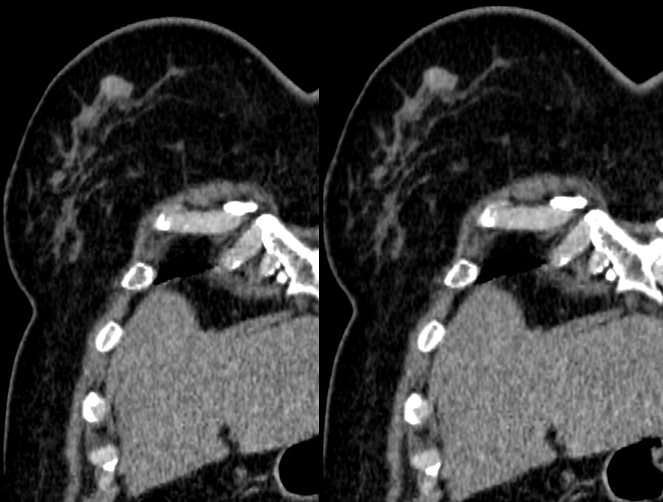

MG/CT:

乳腺炎:包括急、慢性乳腺炎和乳腺脓肿,多见于产后哺乳期妇女,急性乳腺炎常有典型的临床症状-红、肿、热、痛;若治疗不及时可形成慢性乳腺炎或乳腺脓肿。MG 表现片状致密影,边缘模糊,患处皮肤水肿增厚,皮下脂肪层模糊;MRI-T1WI 表现为片状低信号,T2WI 高信号,信号强度不均匀,边缘模糊,皮肤水肿、增厚,增强 MRI 通常表现为轻至中度强化,且以延迟强化为主。